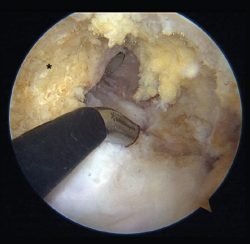

Depending on the preferences and experience of the surgeon, reconstruction of the PCL can be made through different portals. The standard anteromedial and anterolateral portals are routinely used for joint revision surgery and the treatment of associated chondral, ligamentous or meniscal lesions. Some authors use posteromedial and posterolateral portals to adopt a trans-septal approach (Kim's technique) and thus work exclusively from the back of the knee. Other surgeons prefer a portal through the patellar tendon (Gillquist portal) in combination with a posteromedial portal, alternating them as viewing and working portal. Utilization of the transpatellar portal is simpler in the case of combined rupture of the ACL and PCL, since the intercondylar space is completely vacant (Figure 8)(23).

Figure 8. "Vacant" intercondylar space in combined rupture of the anterior cruciate ligament (ACL) and the posterior cruciate ligament (PCL) in a left knee. The surgeon is using the transpatellar (Gillquist) portal for viewing and the anteromedial portal for working with radiofrequency. The working cannula placed in a posteromedial portal can also be seen. The black asterisk indicates the lateral wall of the medial femoral condyle, as the femoral insertion site of the PCL.